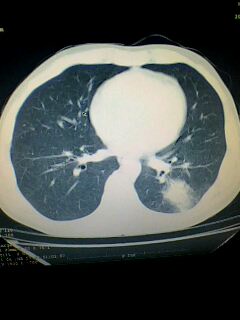

考虑左肺下叶周围型肺癌.图象欠清,请问病人贵更?

考虑左肺下叶周围型肺癌.

图像资料欠清,建议强化,考虑周围型肺癌。

左下肺肿块影,深分叶,考虑肺癌。

左下肺球形病灶,考虑:1:球形肺炎;2:周围型肺癌不除外,建议治疗后复查

不排除左肺下叶周围型肺癌可能!建议穿刺活检!

考虑左肺下叶周围型肺癌。

考虑左肺下叶周围型肺癌并阻塞性肺炎。

考虑左肺下叶周围型肺癌